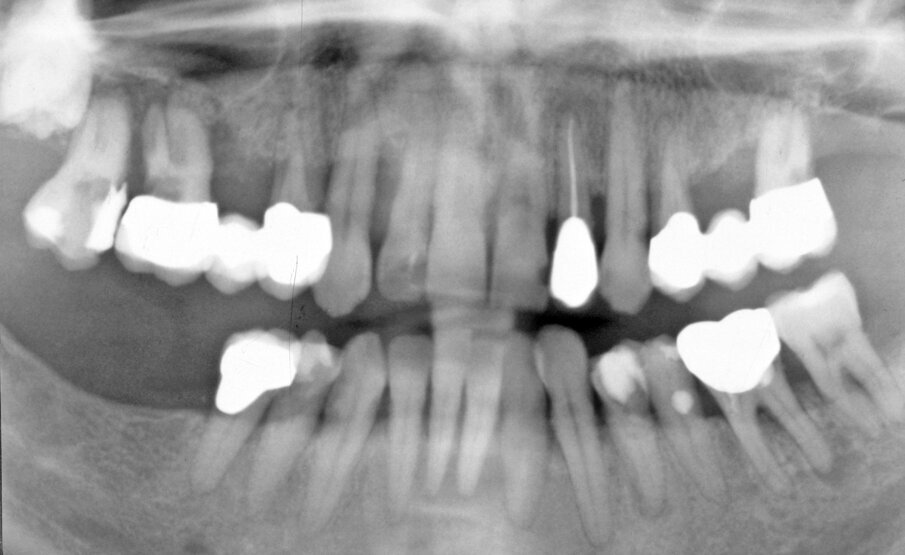

A 55-year-old woman was referred for a complex periodontal-implant treatment (Fig. 1, Fig. 2). Due to severe pain teeth #18–16 and 14 were immediately extracted and the socket #14 was augmented using a non-resorbable membrane (Cytoplast, Regentex GBR-200; Osteogenics Biomedical, Lubbock, TX).5,6

Fig. 1. Initial examination. Orthopantomograph